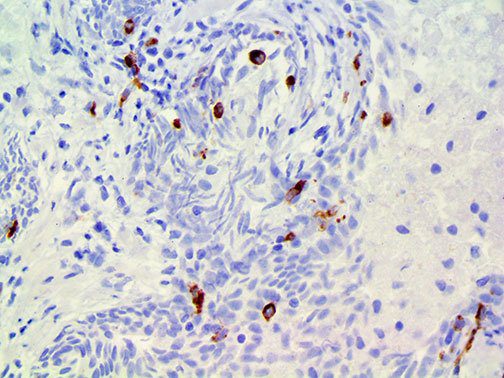

It is the ICU physician who is most likely to witness one of the deadliest manifestations of the abnormal immunological response, the cytokine storm syndrome (CSS). This response is also referred to by some as the cytokine release syndrome (CRS). CSS is characterized by continuous activation and expansion of macrophage and lymphocyte populations, which secrete large amounts of cytokines, causing the cytokine storm. This massive cytokine release is akin to hemophagocytic lymphohistiocytosis (HLH) disease, a syndrome characterized by initial unchecked and persistent activation of cytotoxic T lymphocytes and NK cells.

Clinical and laboratory manifestations of HLH include fever, enlarged liver and/or spleen, neurologic dysfunction, coagulopathy, liver dysfunction, cytopenias (i.e., low levels of erythrocytes, leukocytes, and/or platelets), hypertriglyceridemia, hyperferritinemia, hemophagocytosis, and eventually diminished NK cell activity as the immune system becomes progressively paralyzed. HLH can be familial (primary HLH) or secondary to another disease process (sHLH), such as rheumatic disease, in which it is referred to as macrophage activation syndrome (MAS, characterized by elevated ferritin).